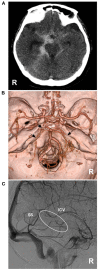

Perimesencephalic nonaneurysmal subarachnoid hemorrhage (PNSAH) is a distinctive disease, representing SAH centered in perimesencephalic cisterns, with negative angiography findings. In recent years, the number of patients with PNSAH has increased significantly; however, the knowledge of PNSAH is insufficient. Therefore, we performed a review of the literature from a PubMed search and recounted our understanding of PNSAH. In this review, we summarized that current high-resolution computed tomography angiography is an acceptable replacement for digital subtraction angiography to rule out aneurysms in PNSAH with strict criteria. The current hypothesis about the etiology of PNSAH is that there is deep vein rupture from aberrant venous anatomy and increased intracranial venous pressure. PNSAH is associated with mild symptoms and lower rates of hydrocephalus and symptomatic vasospasm. For PNSAH, conservative treatment has been the mainstream treatment. PNSAH has a benign clinical course and an excellent prognosis; in long-term follow-up, re-bleeding and death were uncommon.